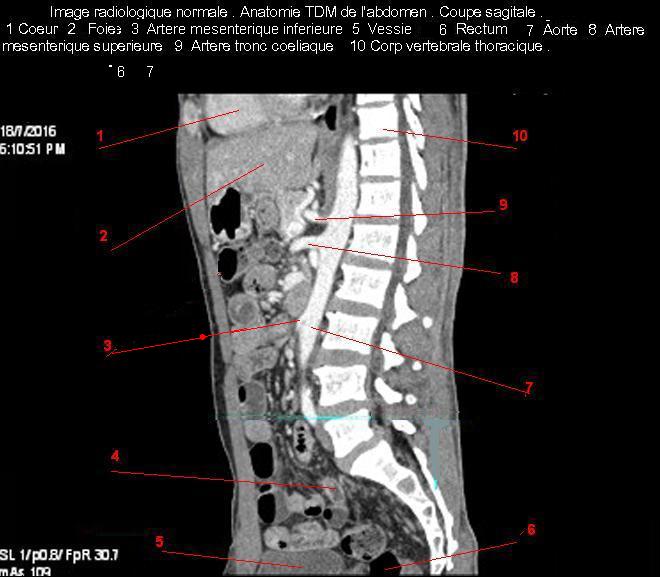

Images radiologique normale de abdomen en coupe sagitale ( CT scanner )  :

Coupe axiale     Coupe frontale      Coupe  sagitale